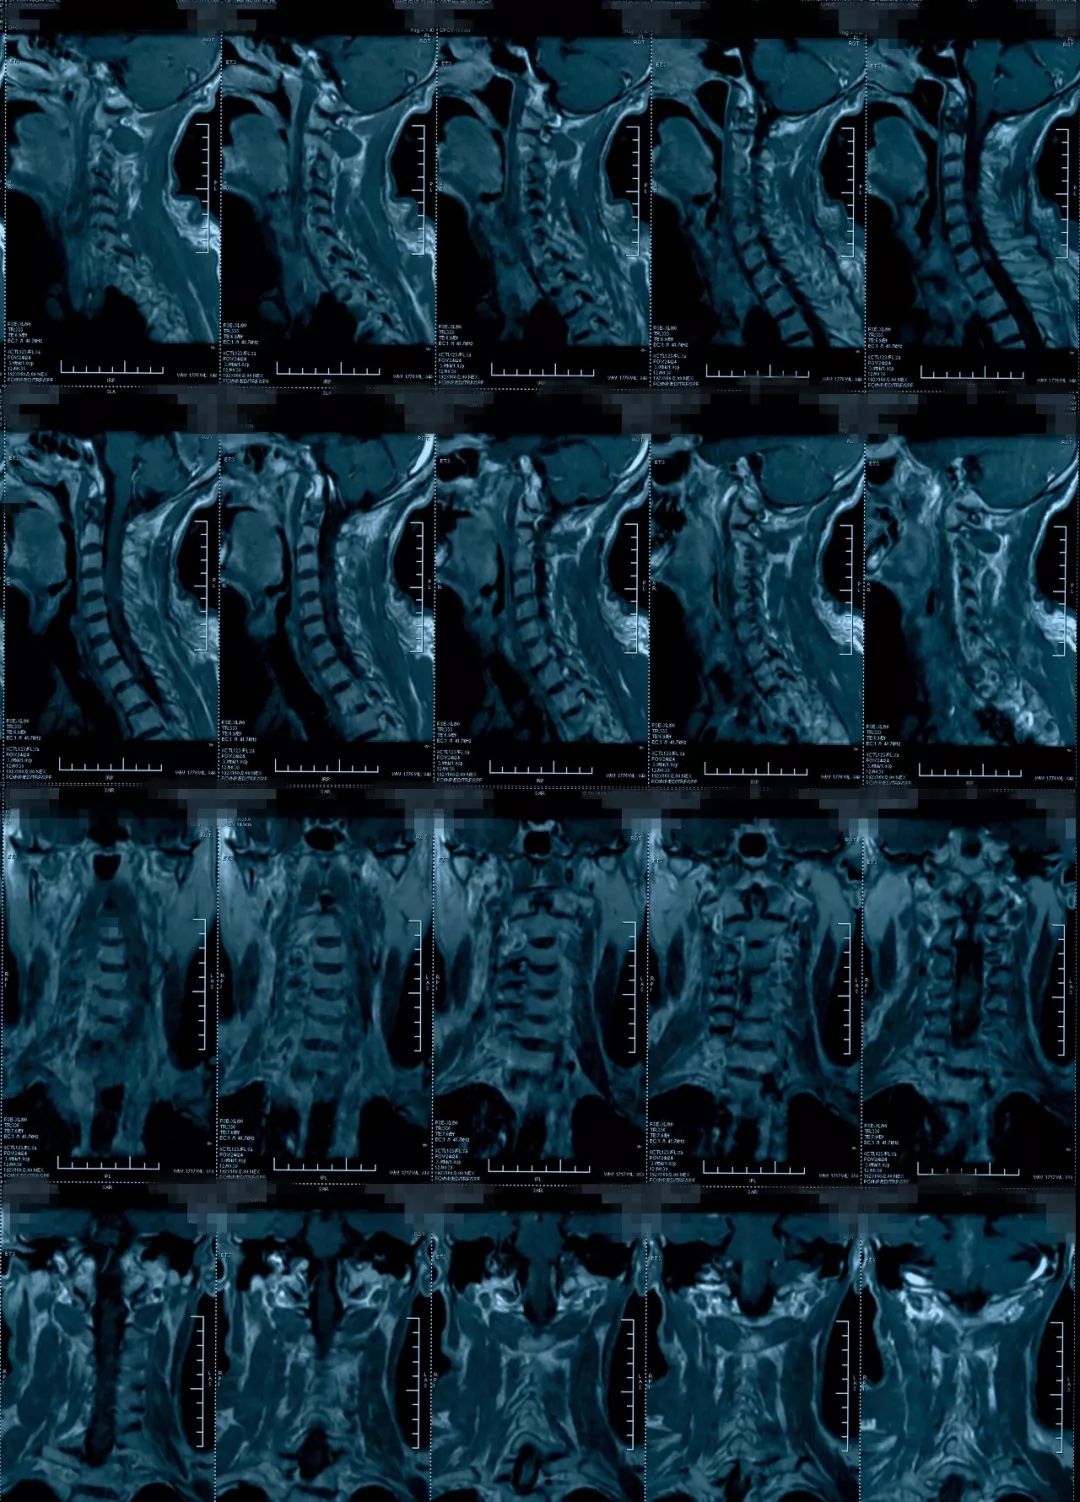

这个病人转到我们科的时候,影像上表现椎管狭窄,脊髓有长阶段的脊髓水肿信号,有黄韧带增厚,后方的间盘有轻度突出,骨质增生等等。

治疗前影像学资料

治疗后影像学资料

病人恢复得挺好,他的椎管是有一些容积减小,更主要是脊髓水肿造成的相对容积减小,如果对这种病人做椎管开大,也是能改善症状,但是毕竟病人做了一个手术,明确炎症之后做保守治疗能够恢复是更好的。明确了病因,病人本人是非常满意的,知道了自己是什么问题,最后得到了很好的治疗。